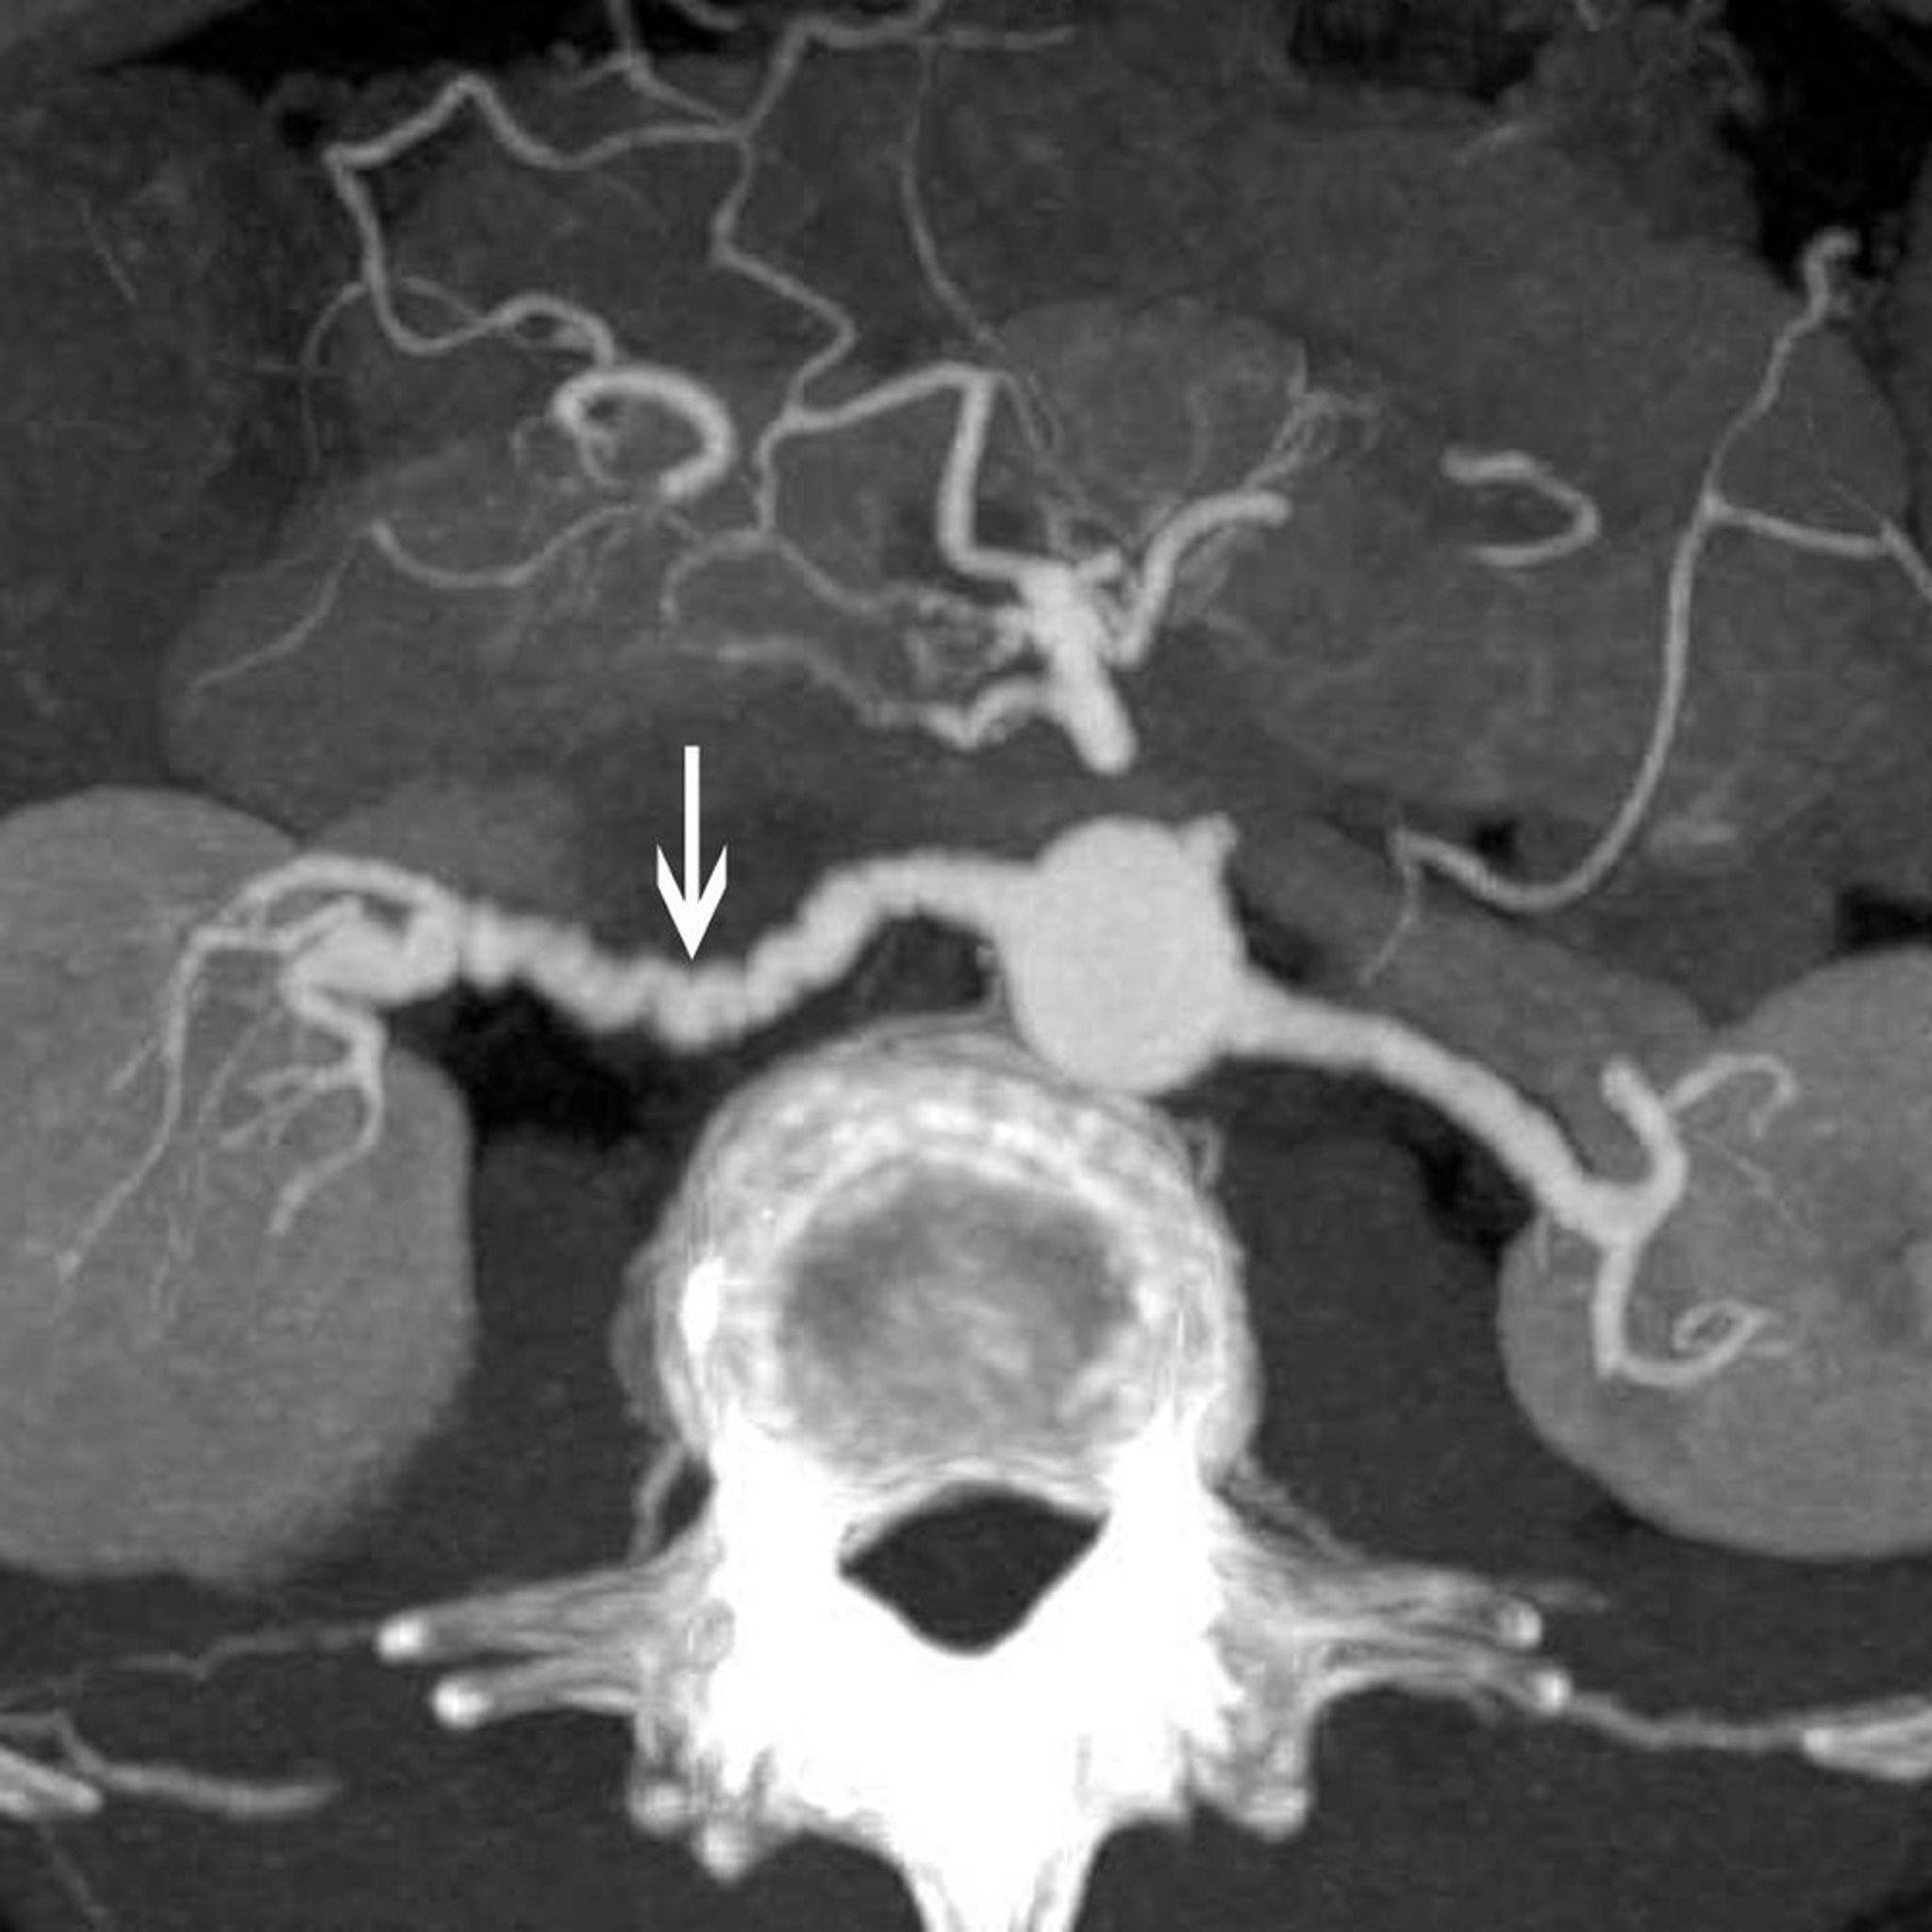

Loạn sản xơ cơ của động mạch thận

Hình ảnh này cho thấy dấu hiệu "chuỗi hạt" cổ điển (mũi tên) ở bệnh nhân mắc chứng loạn sản cơ xơ của động mạch thận.